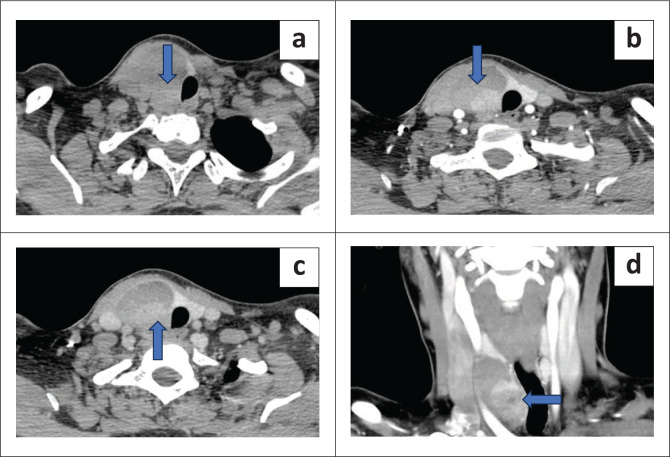

Results: Of the 44 patients who underwent 4DCT, operative findings of three patients were discordant with the 4DCT findings. The calculated sensitivity of 4DCT was 93%. 4DCT was able to identify lesions in ectopic locations in two cases and missed one case in an intra-thyroidal location, misinterpreted as a suspicious thyroid lesion. The sensitivity of 4DCT in detecting multiglandular disease was 75%. Of the diagnosed parathyroid lesions, 52.1% were located on the left, 35.4% on the right and 12.5% were located bilaterally. Additionally, 76% were seen inferiorly and 24% were seen superiorly.

Conclusion: 4DCT has high utility in the presurgical localisation of the eutopically or ectopically placed diseased parathyroid glands in single and multiglandular disease and also provides additional anatomical details.

Contribution: 4DCT identified additional findings such as aberrant origin of right subclavian artery, which is an important pre-operative finding for the surgeon to be aware of. This study contributes to the existing literature on the role of 4DCT.